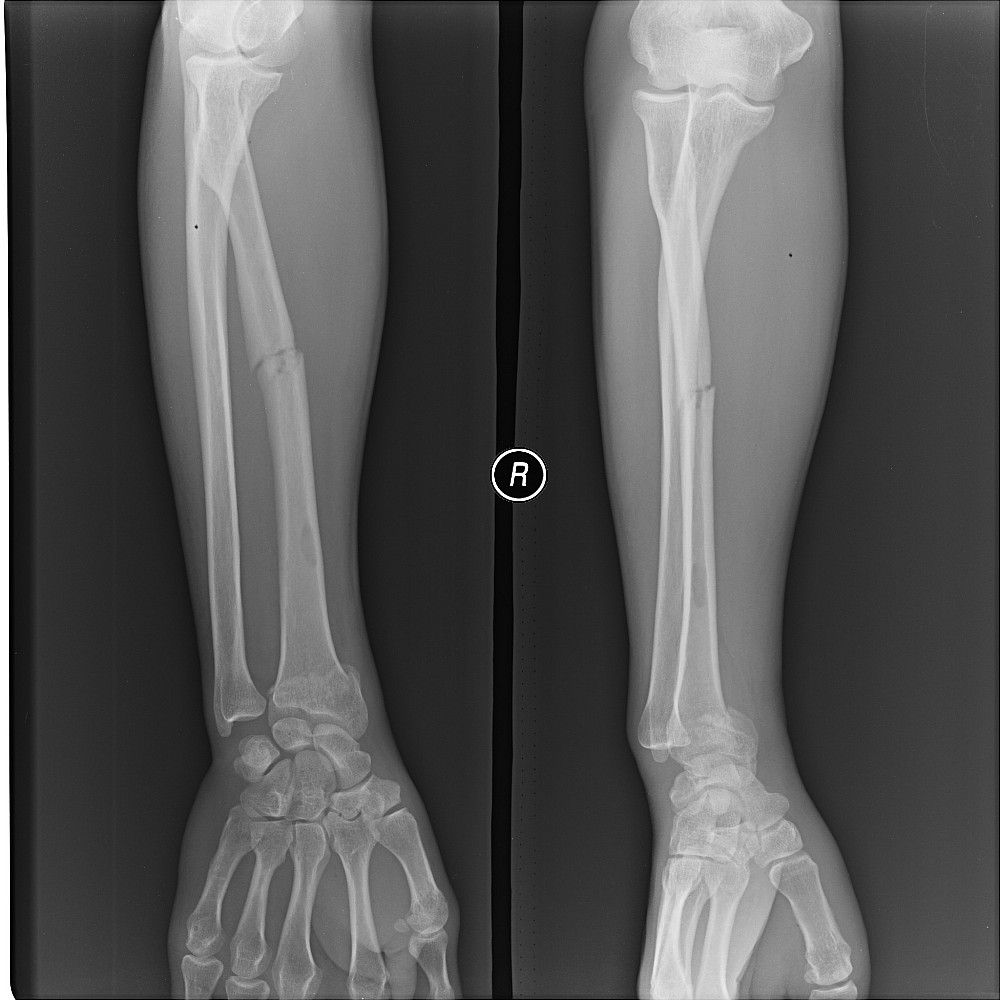

以下是引用yuhongjun在2008-8-21 6:23:00的发言:[br]纤维性骨皮质缺损可能.

以下是引用liaoqiang在2008-8-21 15:41:00的发言:[br]考虑骨囊肿可能性大。

以下是引用黑白光影在2008-8-21 21:03:00的发言:[br]考虑骨囊肿可能性大。骨纤维皮质缺损距关节太远了点且无明显边缘骨质无硬化,病灶部位不表浅。[br][br]